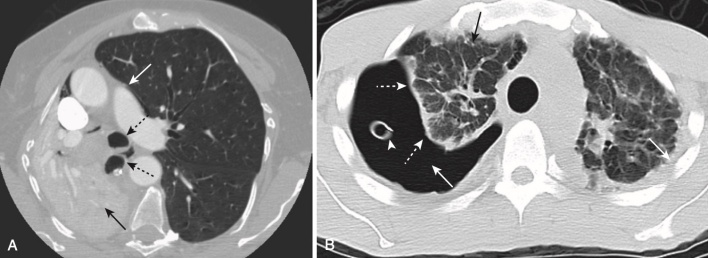

- Ở một bệnh nhân người lớn bị mờ nửa phổi, không có hình ảnh phế quản chứa khí và ít hoặc không có sự dịch chuyển của các cấu trúc lồng ngực di động, cần nghi ngờ một ung thư biểu mô tuyến phế quản gây tắc nghẽn, có lẽ có di căn đến màng phổi. Chụp cắt lớp vi tính (CT) ngực sẽ cho thấy những bất thường này (Hình 5).